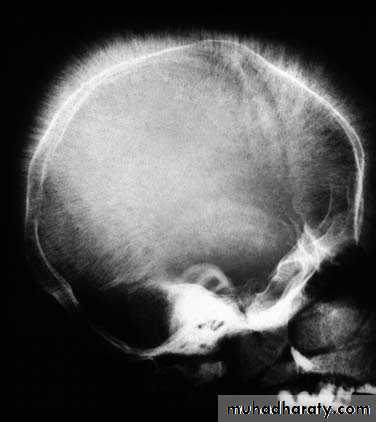

• • Skull radiographs showing hair-on-end appearance due to widening of diploic spaces

• • Abnormal facies, prominence of malar eminences, frontal bossing, depression of bridge of the nose and exposure of upper central teeth